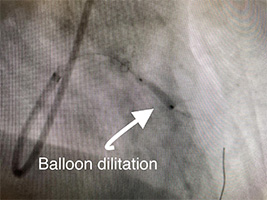

73 y/o female presents with accelerating symptoms of angina. Angiogram pictures show Left Anterior Descending artery (LAD) is severely blocked(stenosed). She receives an initial balloon dilatation and finally a drug eluting stent is implanted (see final result). She no longer has chest pain.